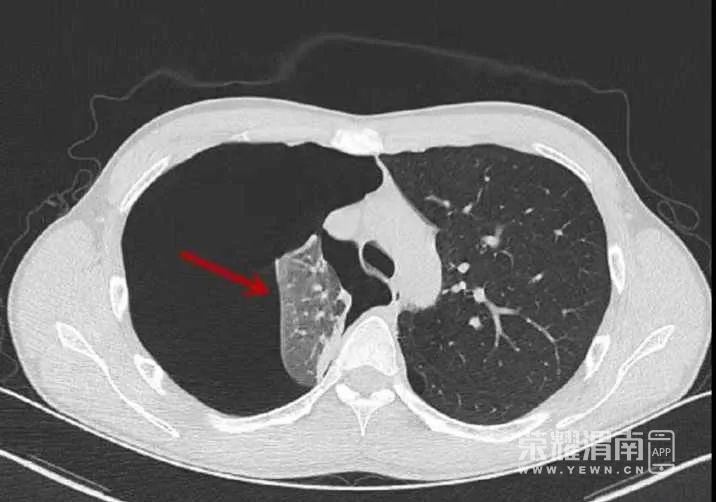

胸部CT提示右侧气胸,右肺犹如被戳破的气球,都已瘪了,肺组织压缩达90%,属于典型的自发性气胸,若不及时抢救会危及生命。

因琐事与父母争吵后,情绪激动,突然觉得右侧胸闷,呼吸困难、轻微胸痛,在附近医院就诊,胸部CT检查提示其右侧气胸,肺组织压缩85%。

医生表示,他在家休息2天后,小邓胸闷等症状未见好转,这才转来医院。复查胸部CT提示肺组织仍压缩85%,急诊予以吸氧、胸腔穿刺闭式引流,后胸闷逐渐缓解。

自发性气胸最简单的诊断方法是胸部X线或胸部CT,可明确气胸的位置及肺组织压缩程度,部分病例可明确肺大疱诊断。